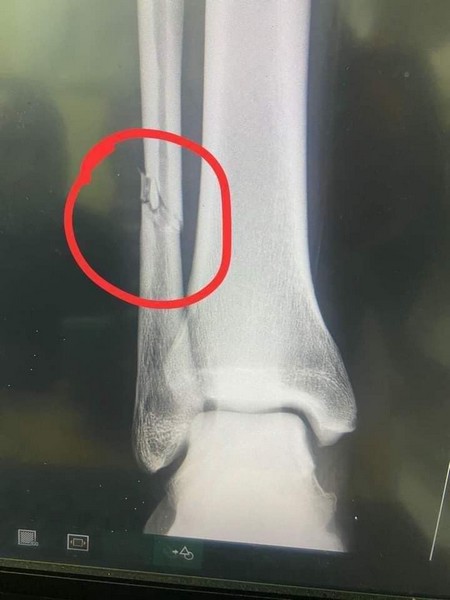

Fracture du péroné pour Adama ba

Rimsport - Après avoir subi un tacle violent d'undéfenseur de Simba Sc, dimanche (13 mars) en match comptant pour la quatrième journée de la Coupe de la Confédération - CAF, Adama Ba a révélé sur les réseaux sociaux souffrir d'une fracture du péroné de la jambe droite.

Un tacle extrêmement violent au tibia du joueur tanzanien, et Adama Ba qui crie de douleur. Les images font froid dans le dos. L'attaquant mauritanien de RS Berkane, revenu au meilleur de sa forme, après sa retraite internationale a été sévèrement blessé.

Sa période d'indisponibilité pourrait dépasser un mois. La défaite des marocains (0-1), en déplacement est forcément passée au second plan après cette grave.